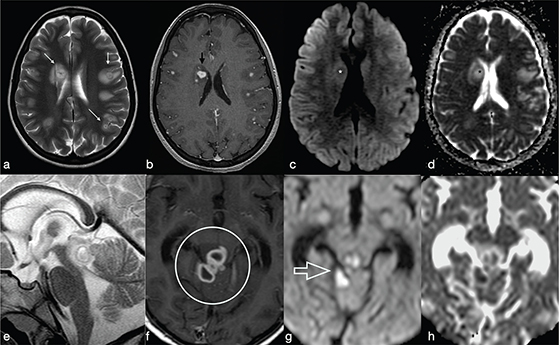

Tuberculous granuloma (tuberculoma) is the most common form of parenchymal CNS tuberculosis. As for pyogenic BA, the cMRI and DWI characteristics depend on the stage of infection: non-caseating, caseating with a solid centre or caseating with a liquid centre (see Table 2). Interestingly, caseating tuberculomas with a liquid centre have an elevated diffusion; indeed, any liquefaction of the central area of necrosis contains a clear fluid, as opposed to pus.7 SWI images may show a complete and regular hypointense peripheral ring.

Tuberculous BA are more similar to pyogenic BA compared to tuberculomas. They usually comprise a multiloculated cavity with central pus, with a thicker wall than a pyogenic BA. It must be distinguished from granuloma with central caseation and liquefaction mimicking pus (Figure 14). However, cMRI does not provide distinction between tubercular and pyogenic BA but lipid peaks without amino acids, on MR spectroscopy, are suggestive of mycobacteria.7

FIG 14. Tuberculoma (a–d) and Tubercular Abscess (e-h). Multiple tuberculomas in both cerebral hemispheres with an hypointense central dot (white arrows in a) within an hyperintense core on T2w are demonstrated. Nodular enhancement on T1+Gd is shown on smaller lesions while the larger one (black arrow in b) shows a thick ring delimitating a cystic core. On DWI and ADC map there is no restricted diffusion (asterisks in c-d). On the contrary, tubercular abscesses located in the quadrigeminal plate show a bright core on T2w, thick peripheral enhancement on T1+Gd (open circle in f) and restricted diffusion on DWI (g) and ADC maps (h).